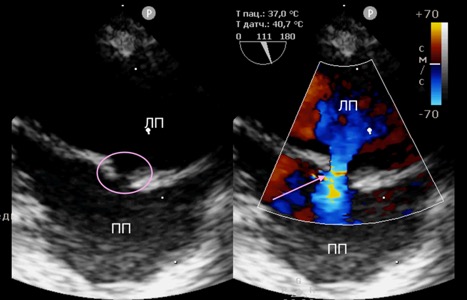

Баллон раздувался до рабочего давления (8–10 атм) в течение 10–15 сек. для создания постоянного сообщения между предсердиями. В ряде случаев требовалась повторная инсуффляция для достижения адекватного диаметра дефекта. В ходе процедуры осуществлялся интраоперационный контроль положения проводника и баллона с использованием эхокардиографического контроля и С-дуги (рис. 3).

Объективным критерием успешности проведения процедуры являлось наличие сброса слева направо, подтвержденного методом цветного доплеровского сканирования(рис. 4), а также снижение давления в левом предсердии, которое оценивалось с помощью катетера, вводимого в левое предсердие. После завершения инсуффляции баллон и проводник удалялись, а сосуд ушивался непрерывным швом.